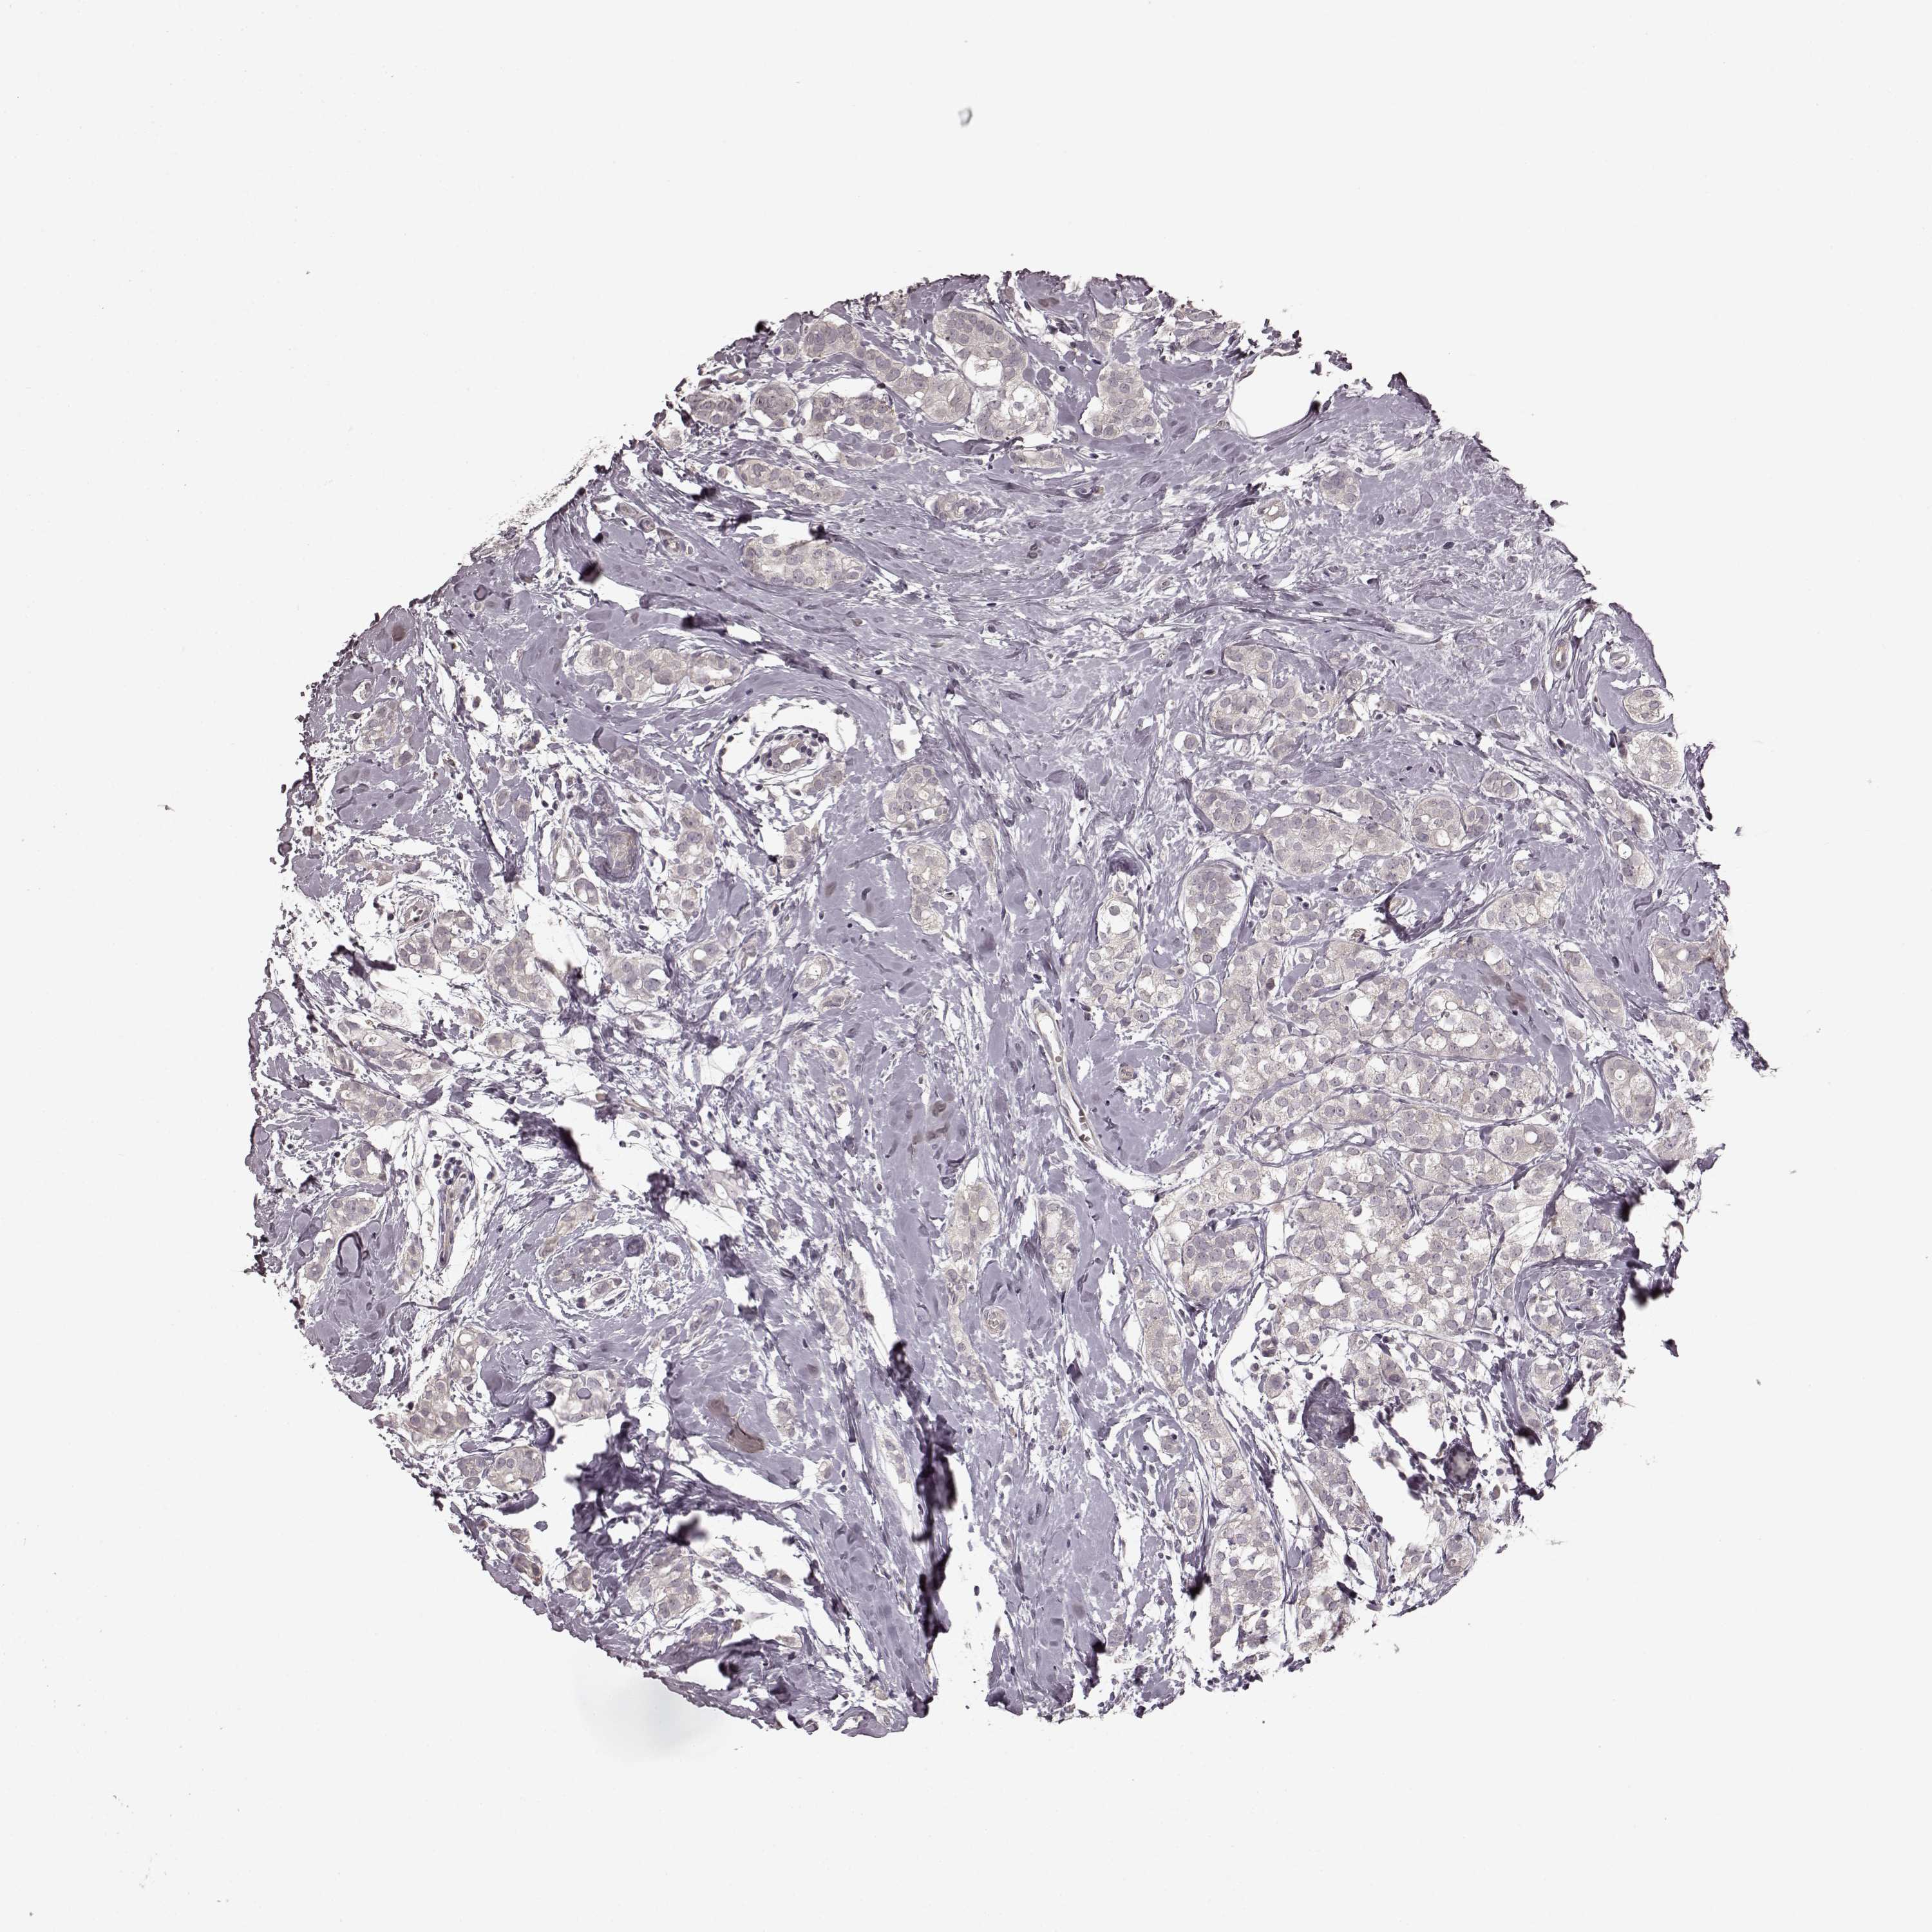

CANCER BREAST CANCER Show tissue menu

BRCA TCGA BRCA VALIDATION PROTEIN EXPRESSION

ANTIBODIES

AND

VALIDATION